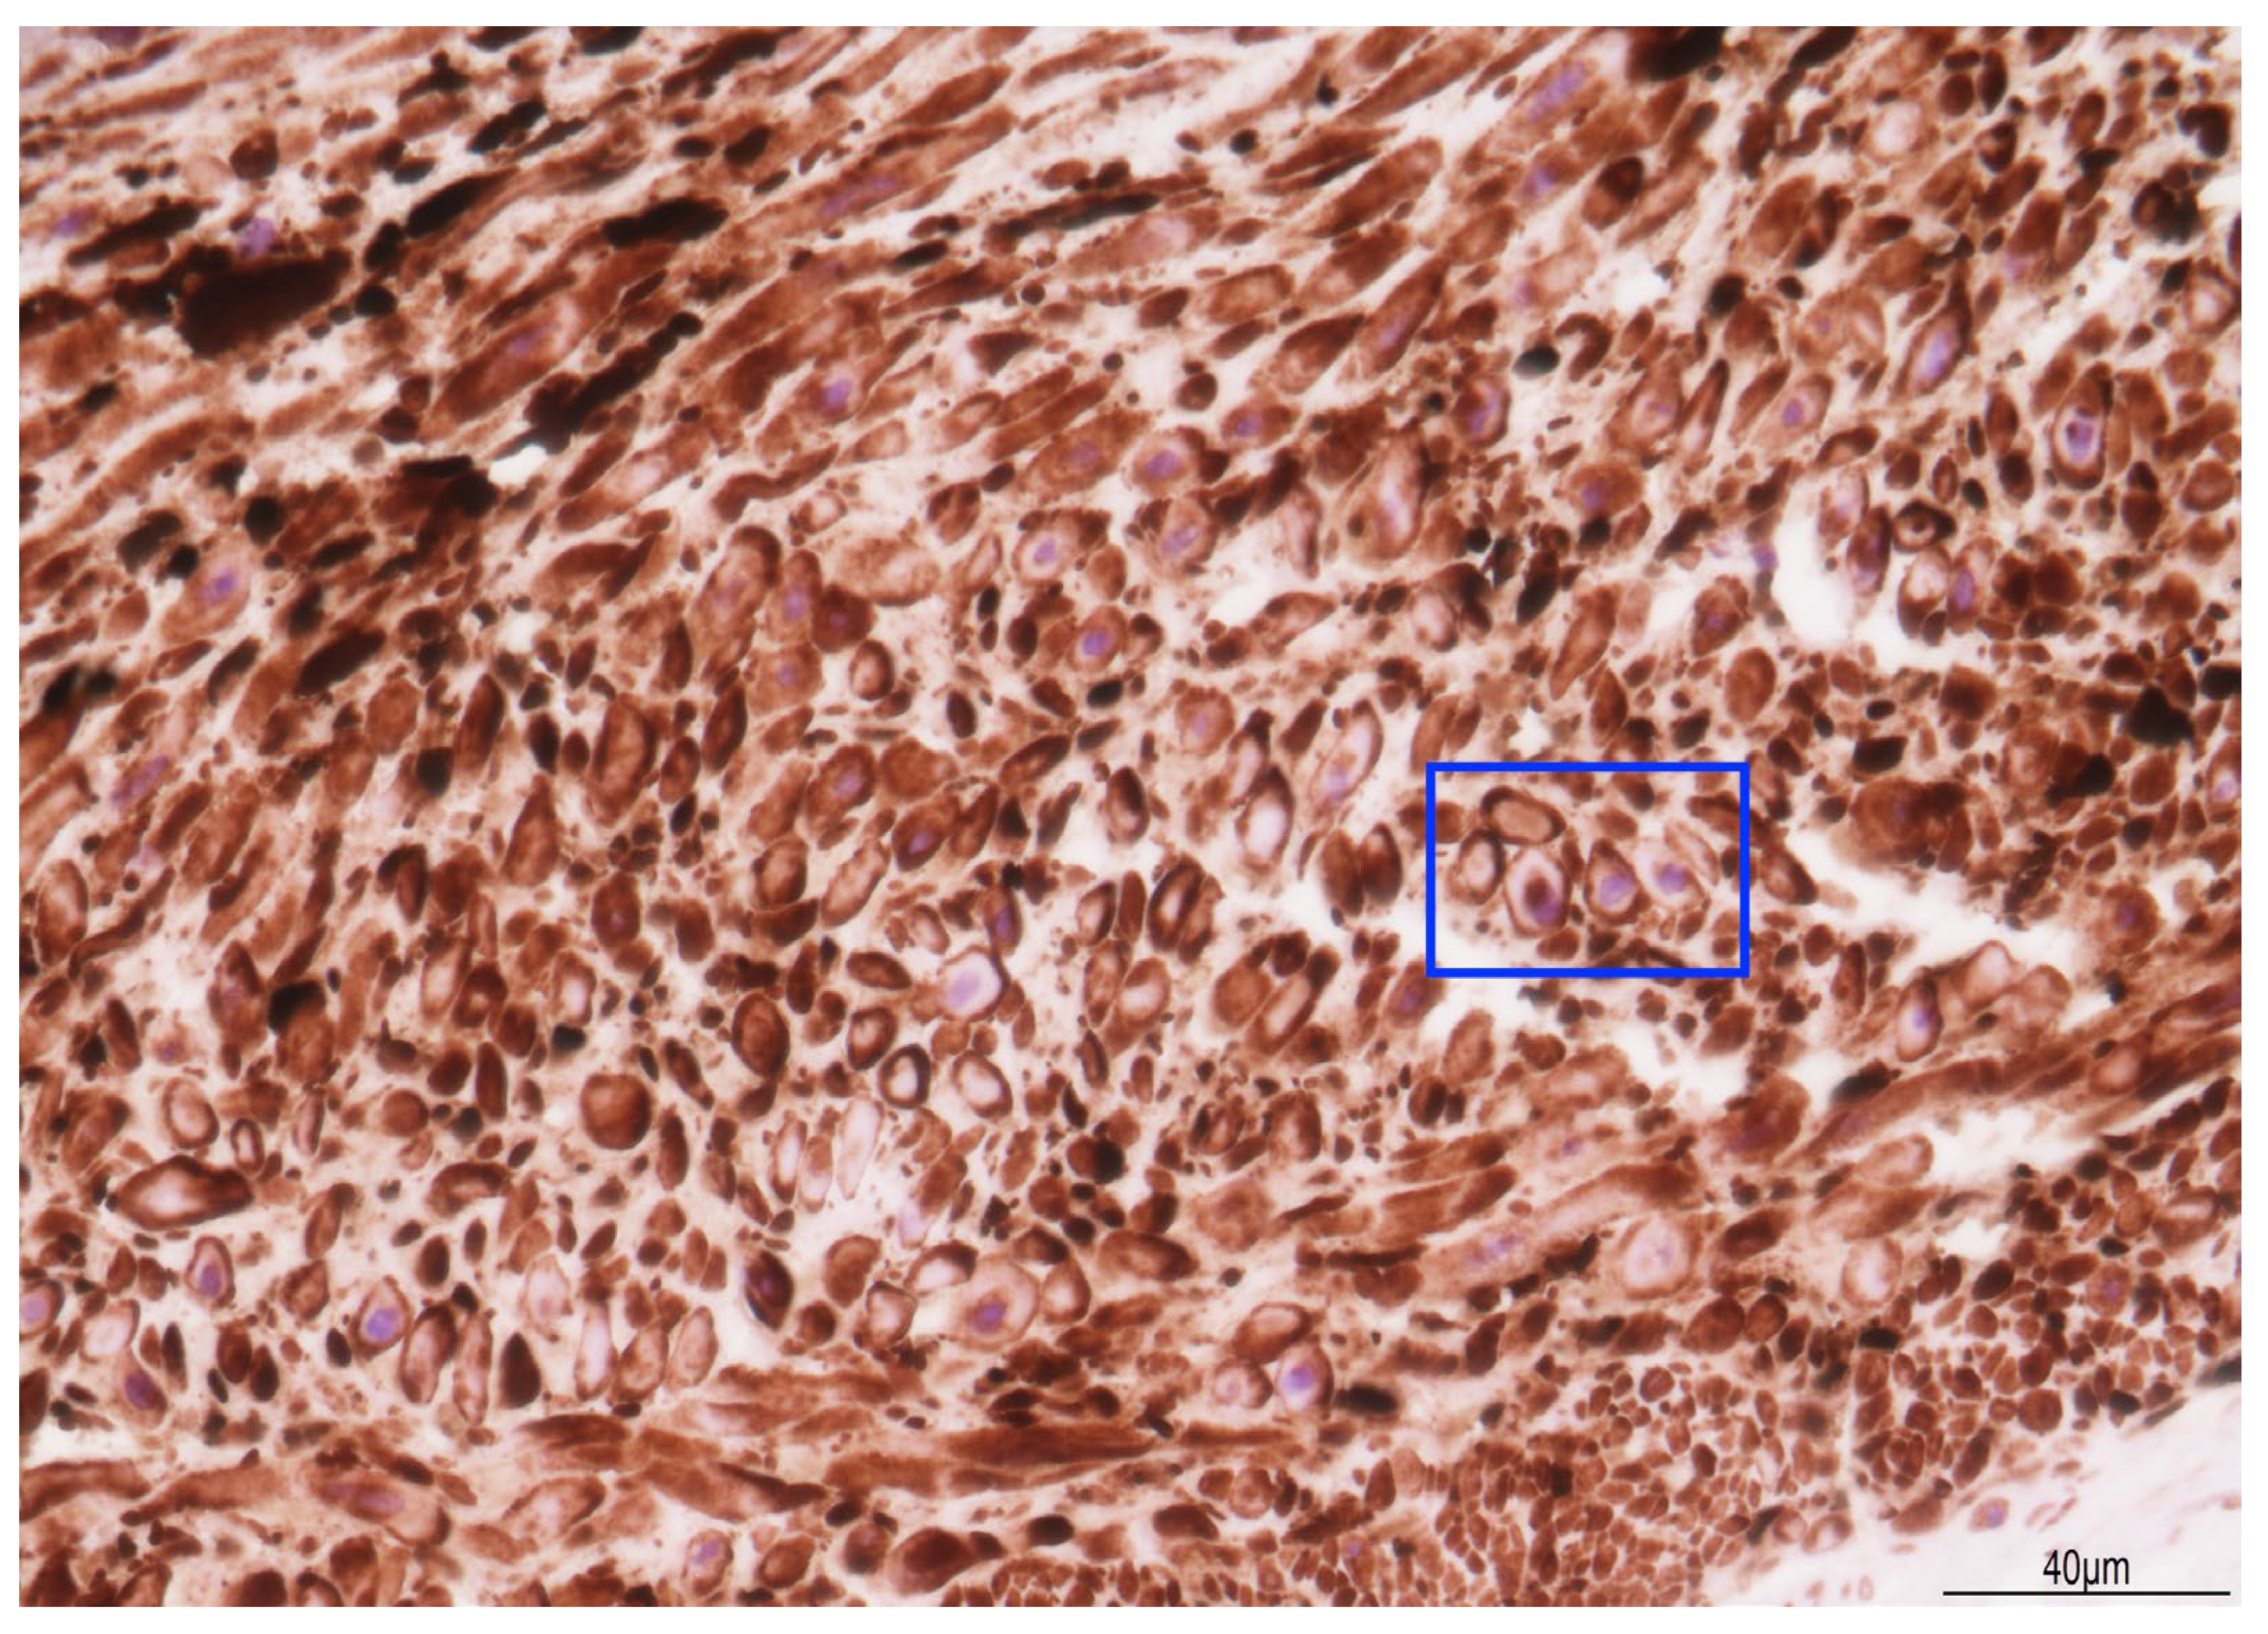

2.2. Fetal Post-Mortem Examination

3.1. The Cause of Fetal Death